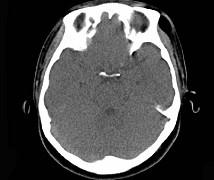

问题 女,31岁,在左眶外上缘发现一包块,质软,余所见无明显异常。如图所示病灶应诊断为 ( )

选项 A、表皮样囊肿 B、淋巴管瘤 C、错构瘤 D、脂肪瘤 E、畸胎瘤

答案 D